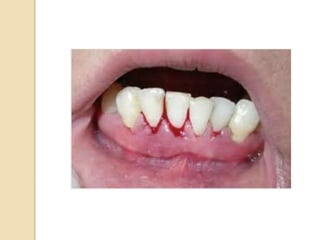

 Laceration of gingiva by toothbrush bristales

during aggressive toothbrushing or by sharp

pieces of hard food can cause gingival

bleeding even in the absence of gingival

disease.